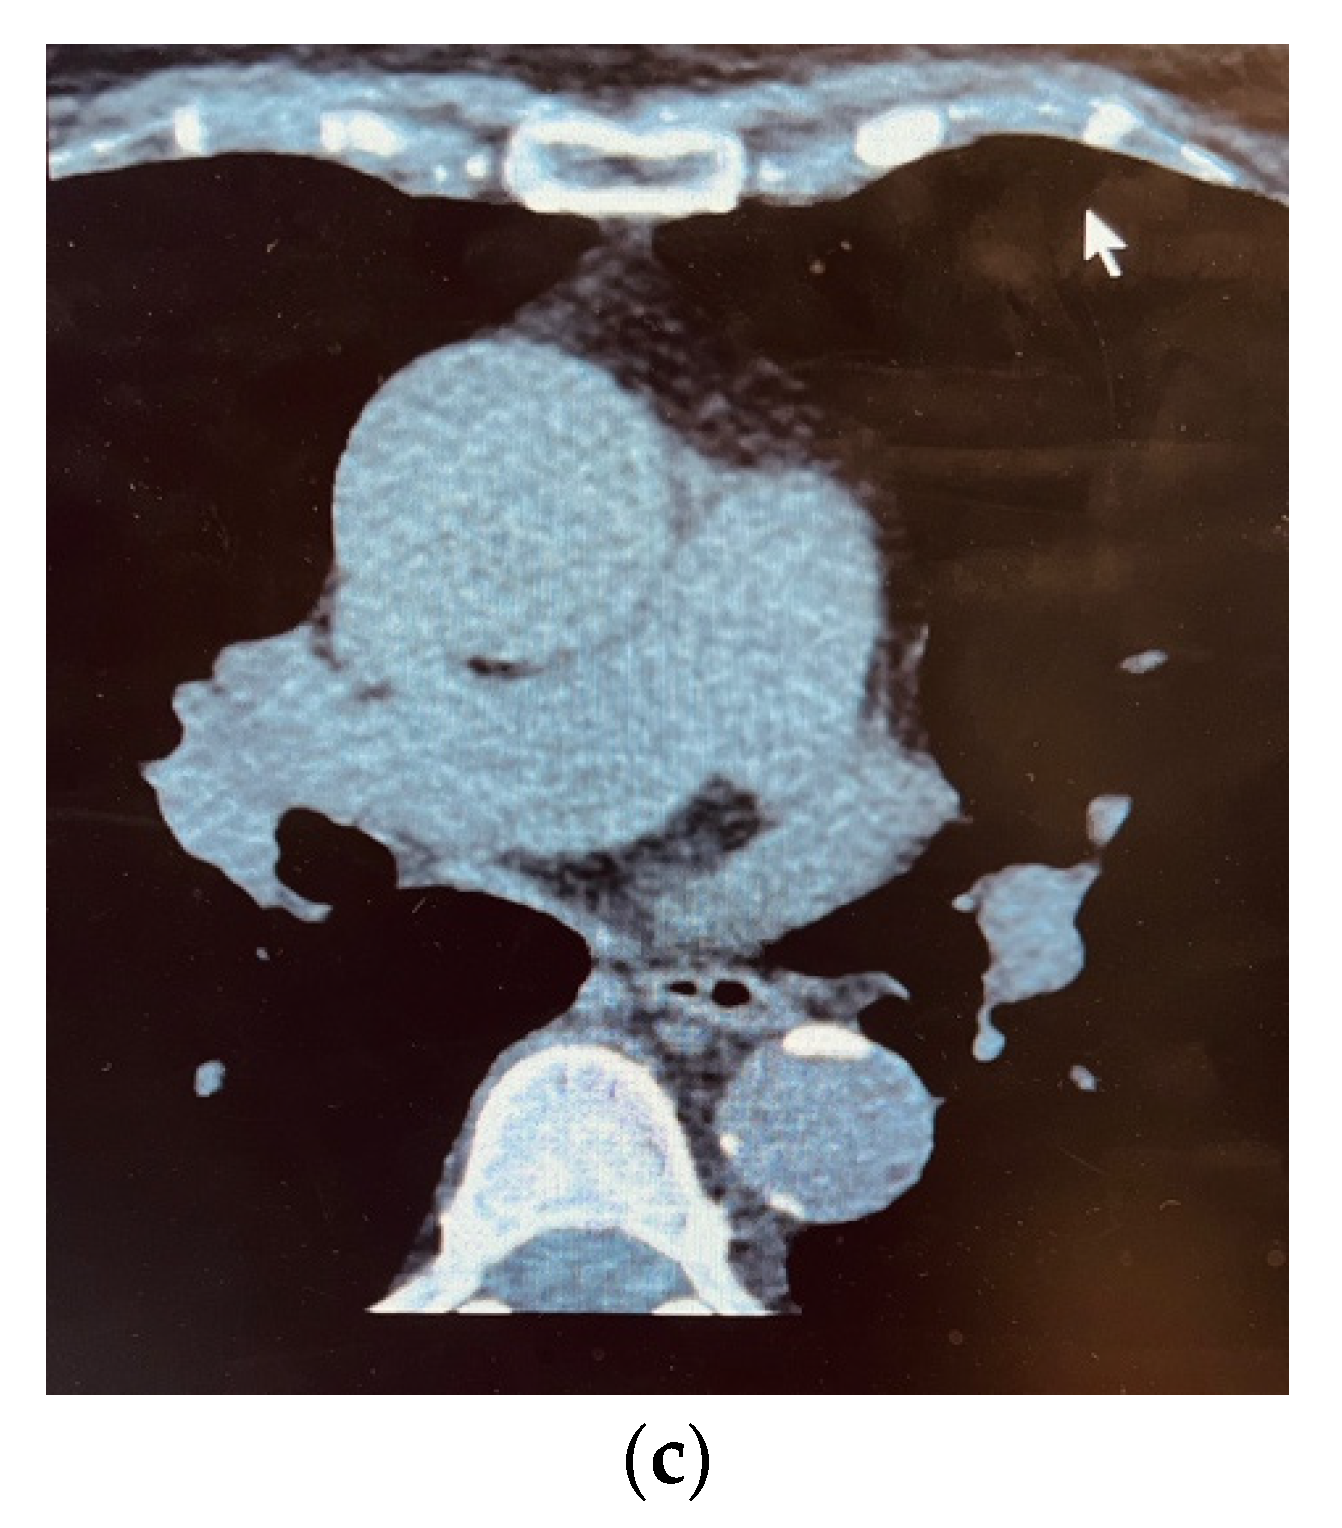

3. Results

4. Discussions